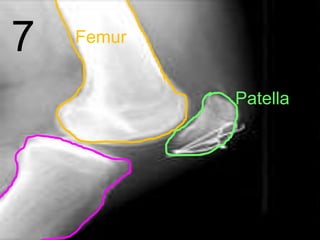

7 Femur

Patella

Tibia